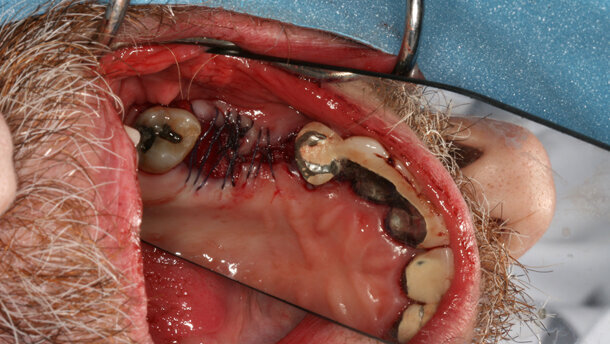

The process involved the harvesting of the stem cells through a small incision in the hip bone of the patient, Jason Morgan, the morning of the procedure. Using a centrifuge, Dr Ho isolated and concentrated Morgan’s stem cells from the plasma and transplanted them into the patient’s jaw and then added an allograft.

During a telephone interview with Dental Tribune after the procedure, Dr Ho explained that the stem cells will work with the surrounding tissue to eventually generate healthy, dense bone tissue to which the dental implant can be permanently attached.

The ultimate goal with this procedure, Dr Ho explained, is to find better, new ways of growing bone. “The stem cells will allow for better quality bone growth and better healing,” he said.